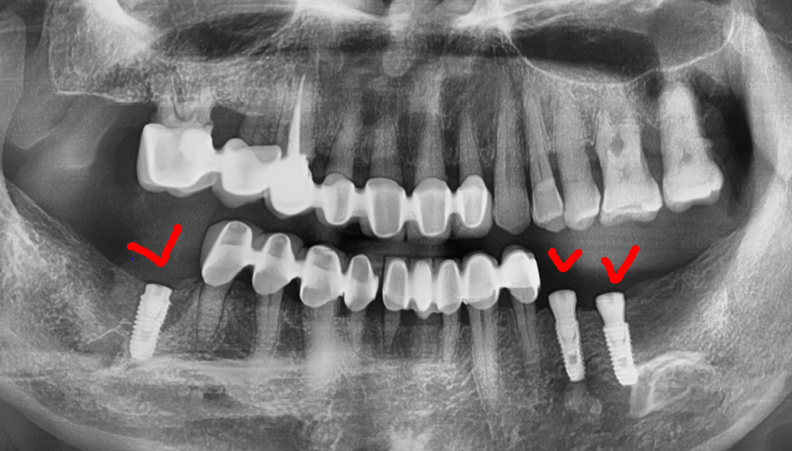

엑스레이를 보면, 아래턱에 어금니들이

결손이 되어있는 것을 볼 수 있습니다.

저희 치과 에 오셔서 임플란트 수술을

의뢰하셨던 분의 엑스레이인데

여튼 위, 엑스레이를 보면서 하나씩 설명드릴게요

1) 이분은, 구강 내 전체적으로 치주염을 앓고

계셨으며 치석 또한 곳곳에 많이 쌓여있었습니다.

따라서, 치조골이 많이 위축 됨에 따라서 하방으로

이동되어 치아의 뿌리가 겉으로 다 드러나

있는 것을 볼 수 있습니다.

다만, 브릿지 보철로 연결이 되어있기 때문에

치아 정출에 관련되어서는 크게 신경 쓸 것은

아니나 추후에는 치료를 반드시 꼭 해야 되는 상황.

2) 1번내용과는 다르게,

상악 어금니만 남아있으며

아래에는 어금니들이 없습니다.

즉, 교합관계를

형성하지 않고 있기 때문에

교합 기능을 전혀 이룰 수 없는 상태입니다.

아울러, 윗니들은 아랫니들이 없기 때문에

점차 아래로 내려오는 ‘치아 정출’ 현상이

지속적으로 나타나면서 추후에 쉽게 발치로

이어지게 되는 상황이 우려됩니다.

따라서, 사진에서 볼 수 있는 것처럼

디지털 임플란트 진단을 실시했으며

치과 에서 총 3개의 임플란트 시술 결정을

내리게 되었었습니다.

다만 이 분은, 치조골이 폭이 많이

위축이 되어있엇던 상황입니다.

왜 이럴까요?

바로 치아가 빠진지 시간이 상당히 흘렀기 때문이죠.